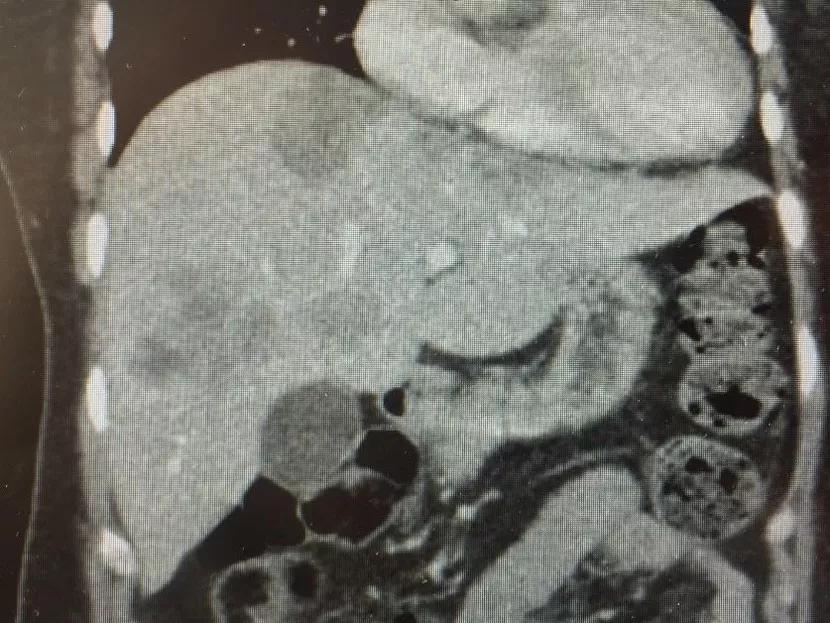

LiverTransProt-Fig-1

Once the new protocol was developed, Cleveland Clinic found a perfect candidate for the first surgical application. This patient had unresectable metastases in the liver as well as liver disease from long-term chemo toxicity. The patient’s cousin served as the live liver donor. Following the successful procedure, both patient and donor were discharged from the hospital within the expected time frame.